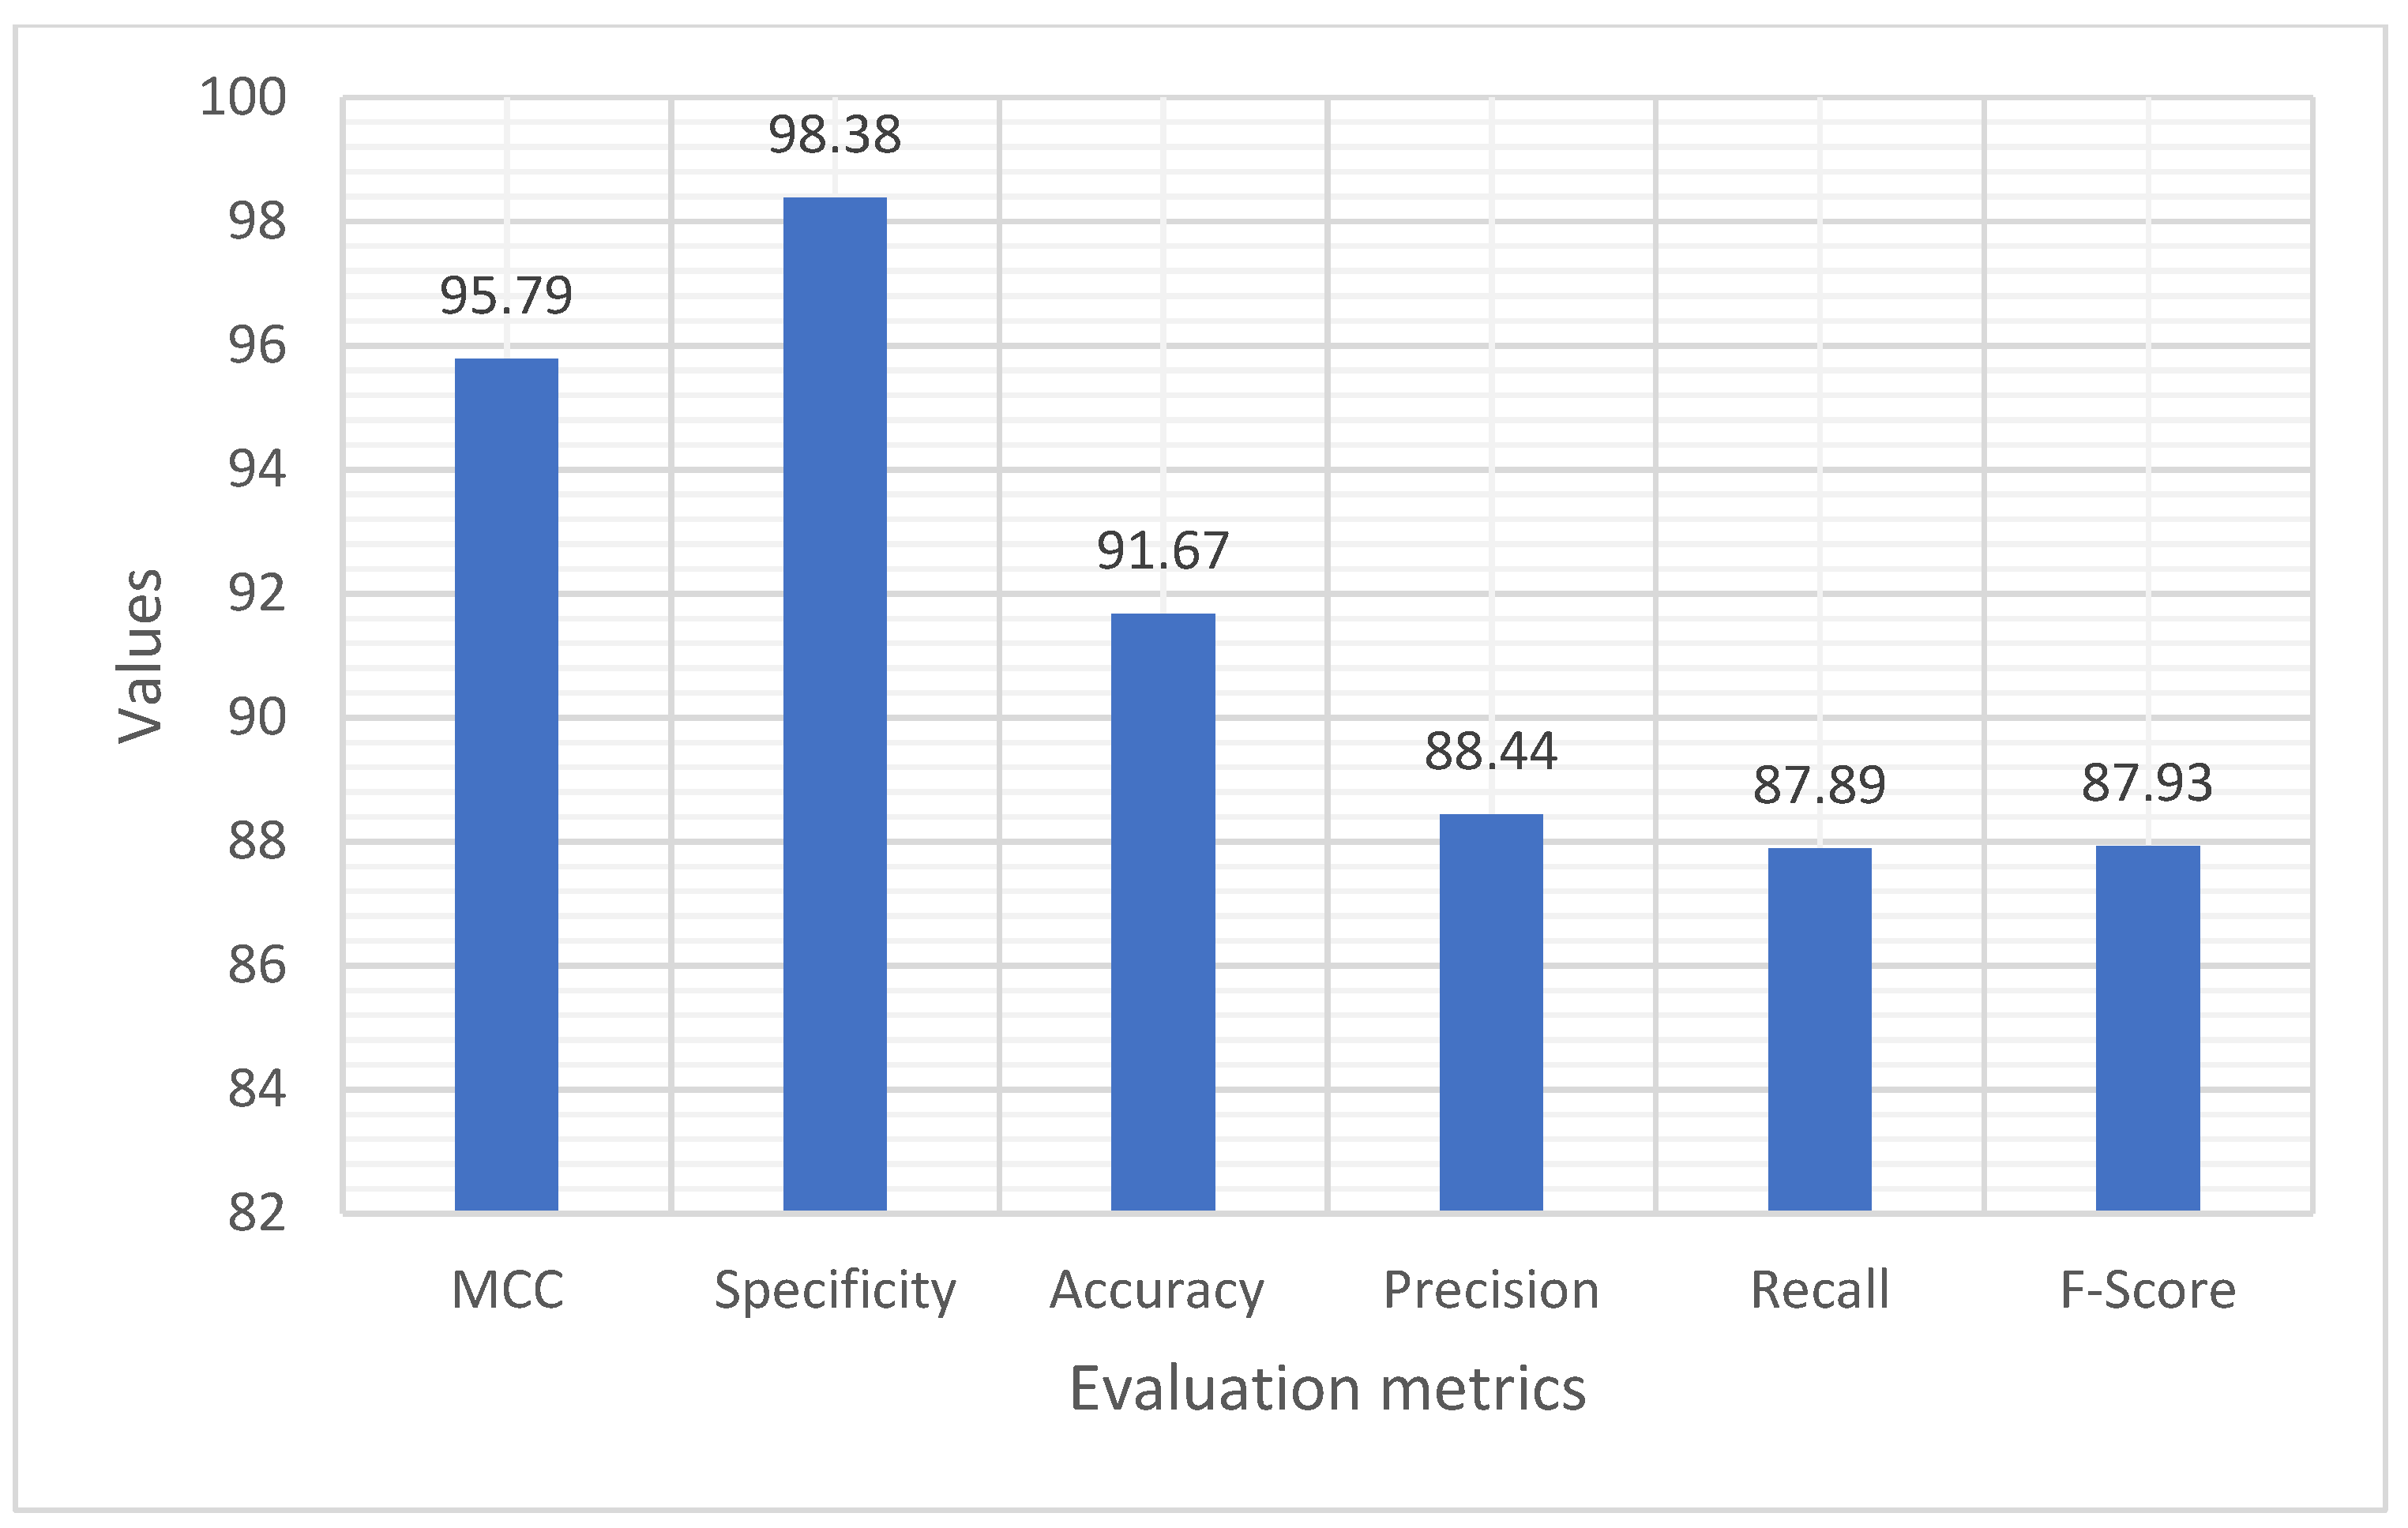

4.1. Performance Evaluation Using Training and Testing Data with Distinct Classes

| Training/Testing-70:30 | ||||||

|---|---|---|---|---|---|---|

| MCC | Specificity | Accuracy | Precision | Recall | F-Score | |

| Normal | 92.34 | 100.00 | 90.28 | 96.18 | 98.16 | 85.45 |

| Malignant | 96.15 | 97.88 | 93.56 | 88.29 | 90.58 | 89.42 |

| Benign | 98.78 | 98.15 | 91.19 | 100.00 | 74.94 | 86.71 |

| Average | 95.79 | 98.38 | 91.67 | 88.44 | 87.89 | 87.93 |